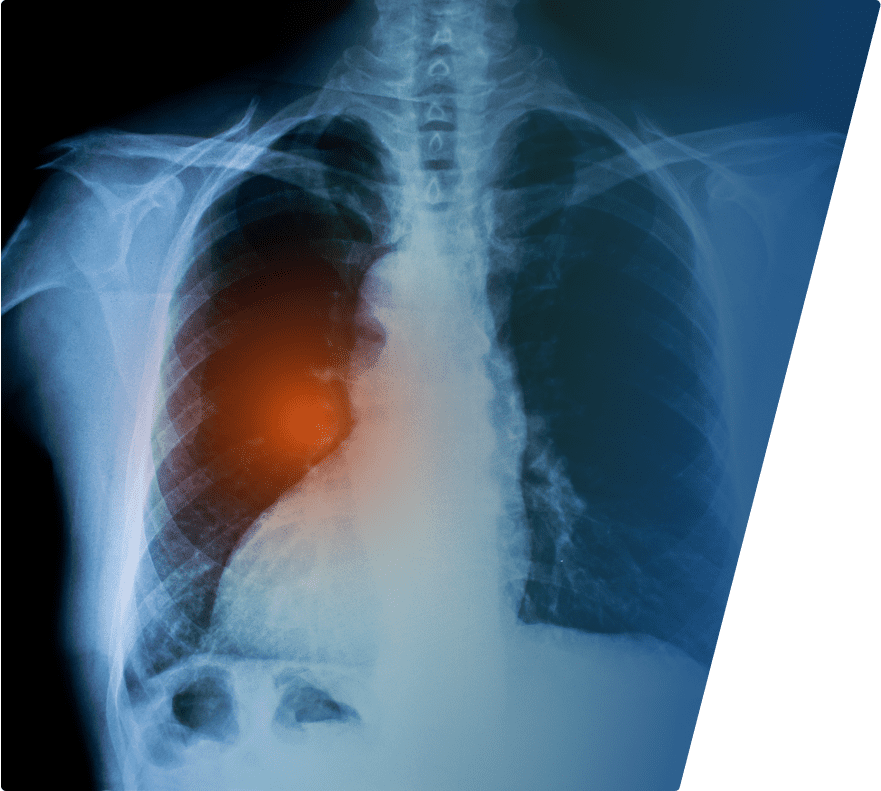

Unknowingly inhaling or swallowing these microscopic fibers causes severe damage as our bodies struggle to get rid of them. Over decades, the trapped fibers trigger biological changes in the tissue that can cause inflammation, scarring and genetic damage that sometimes leads to cancer. Asbestos fibers most often become trapped in either the inside of the lungs, called the parenchyma, or the lining of the lungs, called the pleura. They also can migrate through the lymphatic system to collect in the lining of the abdominal cavity (peritoneum) or heart (pericardium), and in very rare circumstances, the lining of the testicles. The lengthy gap between asbestos exposure and diagnosis, which can range from 20-50 years, is called the latency period. Unfortunately, your exposures to asbestos from long ago may have already determined your likelihood of developing mesothelioma or lung cancer.